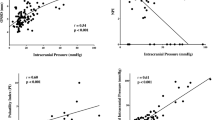

Correlation

There was a negative linear correlation between DI and ICP (R = − 0.28; 95% CI R < − 0.03; p = 0.03) and a positive linear correlation between ONSD and ICP (R = 0.45; 95% CI R > 0.23; p < 0.01). When including ONSD and DI in a multiple linear regression, the estimated correlation coefficient increased (R = 0.51; 95% CI R > 0.30; p < 0.01), compared to using ONSD alone. However, the model improvement did not reach statistical significance (p = 0.09). The linear regressions with associated R2 values are shown in Fig. 2.

Analysis by dichotomization at ICP ≥ 15 mm Hg (high ICP ≥ 15 mm Hg: n = 27; low ICP < 15 mm Hg: n = 17) showed a significant difference in both median DI and ONSD between the groups (Fig. 3). For DI alone, the AUC was 0.69 (95% CI 0.53–0.83), whereas the AUC for ONSD alone was 0.72 (95% CI 0.56–0.86). When including DI and ONSD in a combined model, the estimated AUC increased (0.80, 95% CI 0.63–0.90) as compared to using ONSD alone, and when comparing the models, the combined model distinguished dichotomized ICP significantly better than the model using ONSD alone (p = 0.02). ROC curves are shown in Fig. 4.

For an ICP threshold of ≥ 20 mm Hg (high ICP ≥ 20 mm Hg: n = 4; low ICP < 20 mm Hg: n = 40), both median DI and ONSD were significantly different between groups (Fig. 3). ROC analysis gave an AUC of 0.75 (95% CI 0.58–0.90) for DI alone and an AUC of 0.78 (95% CI 0.52–0.93) for ONSD alone. When including DI and ONSD in a combined model, the estimated AUC increased to 0.86 (95% CI 0.67–0.96), as compared to when using ONSD alone. However, the model improvement did not reach statistical significance (p = 0.11). ROC curves are shown in Fig. 4.

Analyses by image quality score showed that when including only examinations in which image quality was deemed adequate (green image quality), the correlation between DI and ICP increased as compared to that of all examinations. Conversely, in the red image quality group (image quality deemed too poor), we found no correlation between DI and ICP. Results are shown in Fig. 5.

When repeating the comparison between the combined regression model including both DI and ONSD and the model using ONSD alone from the primary analysis, but with only examinations of green image quality included, the combined model now correlated significantly better to ICP compared to the model using ONSD alone (p = 0.03).